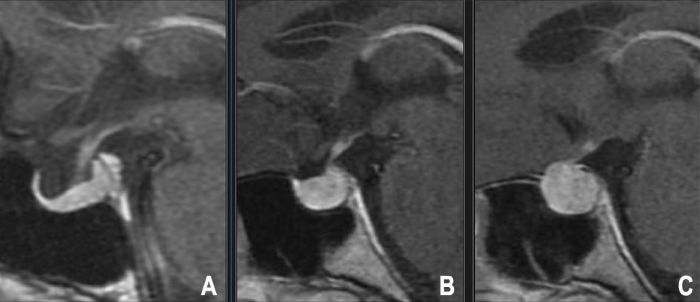

ნორმალური ჰიპოფიზის ზომა მკვეთრად იცვლება ქალებში ასაკის და ორსულობის დროს, რაც ნაჩვენების ჰიპოფიზის მაგნიტურ-რეზონანსულ ტომოგრაფიაზე. A — მოხუცი ქალი, B — ნორმალი ახალგაზრდა ქალი, C — ქალი მშობიარობის შემდგომ.